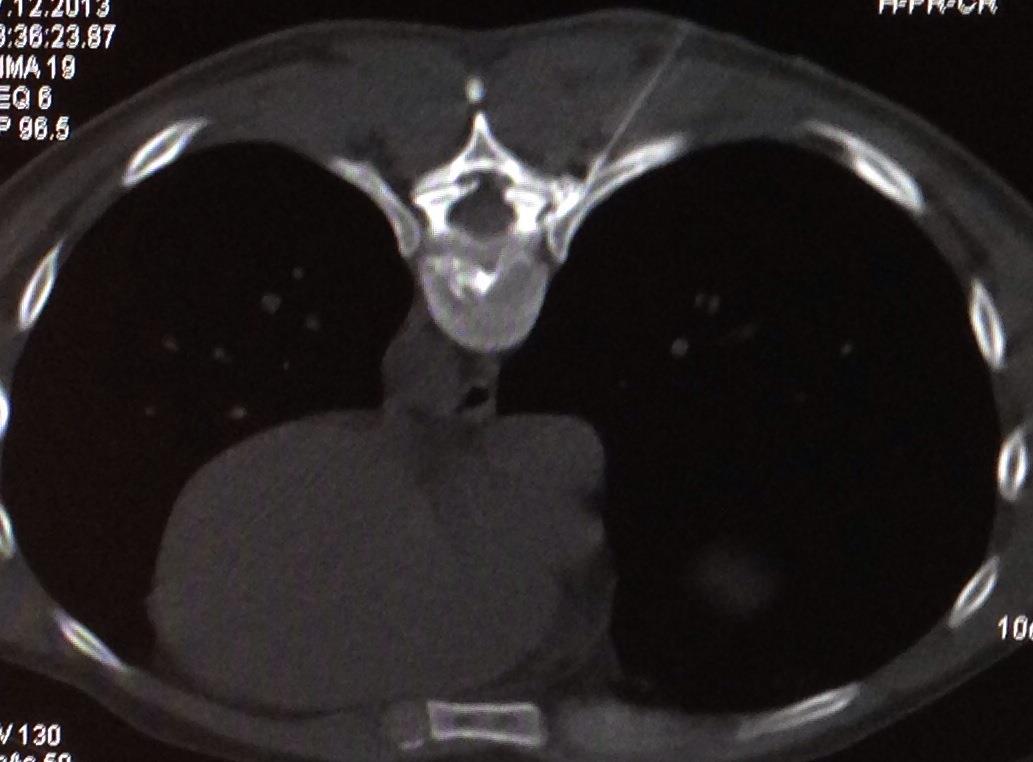

With the help of an X-ray the surgeon inserts a thin needle into the intervertebral disk. Due to the administration of analgetics the entire intervention is nearly pain free. By the help of the needle the surgeon can then insert a glass fiber which carries a laser. The slipped disk can then be vaporized by a laser.

The surgeon will insert a very small needle into the painful joint and will be guided by an X-Ray control. With the help of the needle where a small laser fiber can be inserted the surgeon can now desolate the nerve which causes the pain.